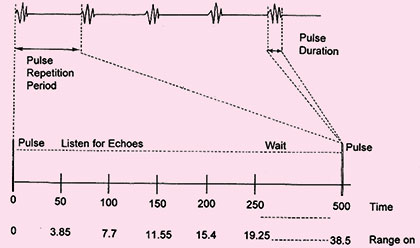

As the frequency of ultrasound used in diagnostic application is about 1 MHz or 1000000 cycle/sec. The duration of emitted sound pulse is one micro second (1 μ sec), and these pulses are repeated about 1000 times per second (PRF=1KHz) (Fig. 1.2).

Fig. 1.2: The pulse-echo timing of data acquisition depicts the initial pulse occurring in a very short span (the pulse duration) and the remained of the time listening for echoes before the next pulse (the pulse repetition period)